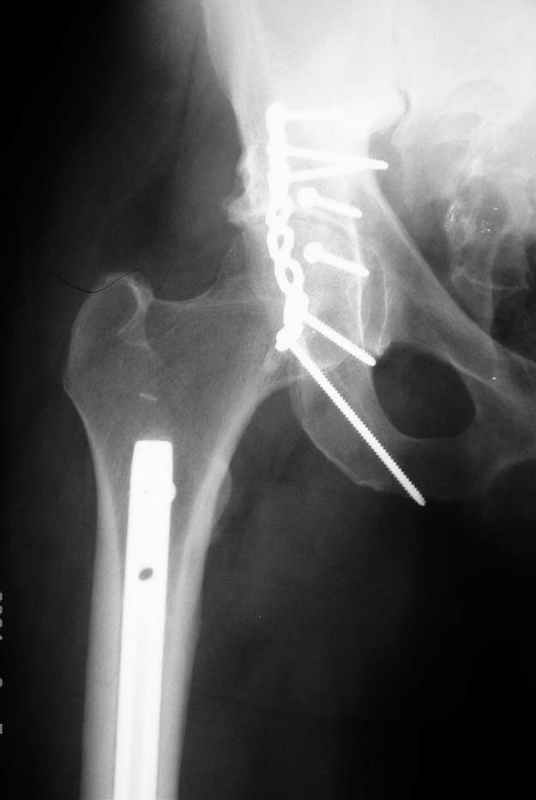

перелом крыла правой подвздошной кости, перелом обеих колонн вертлужной впадины, двусторонний перелом лонных костей (С2.2) повреждение передних связок правого крестцово-подвздошного сочленения,

ипсилатеральный перелом шейки и диафиза бедра.

К сожалению, набора для ретроградного или антеградного реконструктивного штифтования в операционной нет, поэтому доставка заняла н-ное время. Вопрос, который возник у меня- по поводу оптимальной тактики хирургии: вся фиксация в один этап из расширенного доступа или последовательно сначала бедро и позже реконструкция впадины, комбинированный доступ к впадине отдельно к передней и задней колоннам или из расширенного илеофеморального одного доступа. Все-таки решил остановиться на одноэтапном подходе и спустя 5 дней (как раз и наборы привезли) из расширенного илеофеморального доступа сначала фиксировал реконструктивным штифтом Smith&Nephews бедро и

шейку (благо перелом шейки 2 типа -относительно стабильный) затем фрагмент крыла подвздошной кости Lag screw, далее пластина на заднюю колонну и винты в переднюю колонну.(с размерами и направлением винтов ошибка вышла:-((, но интраоперационно у меня была полная уверенность , что винты *ушли* в лонную кость).

Еще раз спасибо за комментарии и готовность помочь с имплантами. Постоп картинки в приложении,